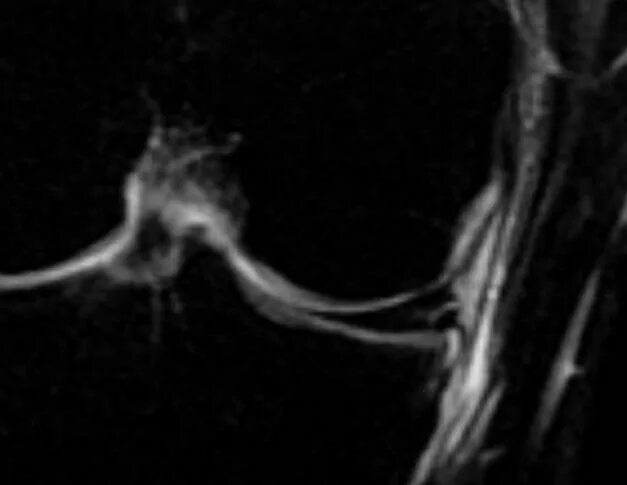

Мрт суставов старый оскол